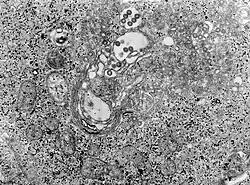

A doença é causada pelo vírus RVF, que é do tipo Phlebovirus. A contaminação ocorre tanto pelo contato com o sangue do animal infectado quanto por respirar o ar perto do animal sendo cortado, beber o leite cru de um animal infectado, ou a picada de um mosquito infectado. Animais tais como vacas, ovelhas, cabras, e camelos podem ser afetados. Nestes animais a contaminação na maior parte é por mosquitos. Não parece que uma pessoa infectada possa infectar outra. O diagnóstico é feito pela identificação de anticorpos contra o vírus ou do próprio vírus no sangue.[1]